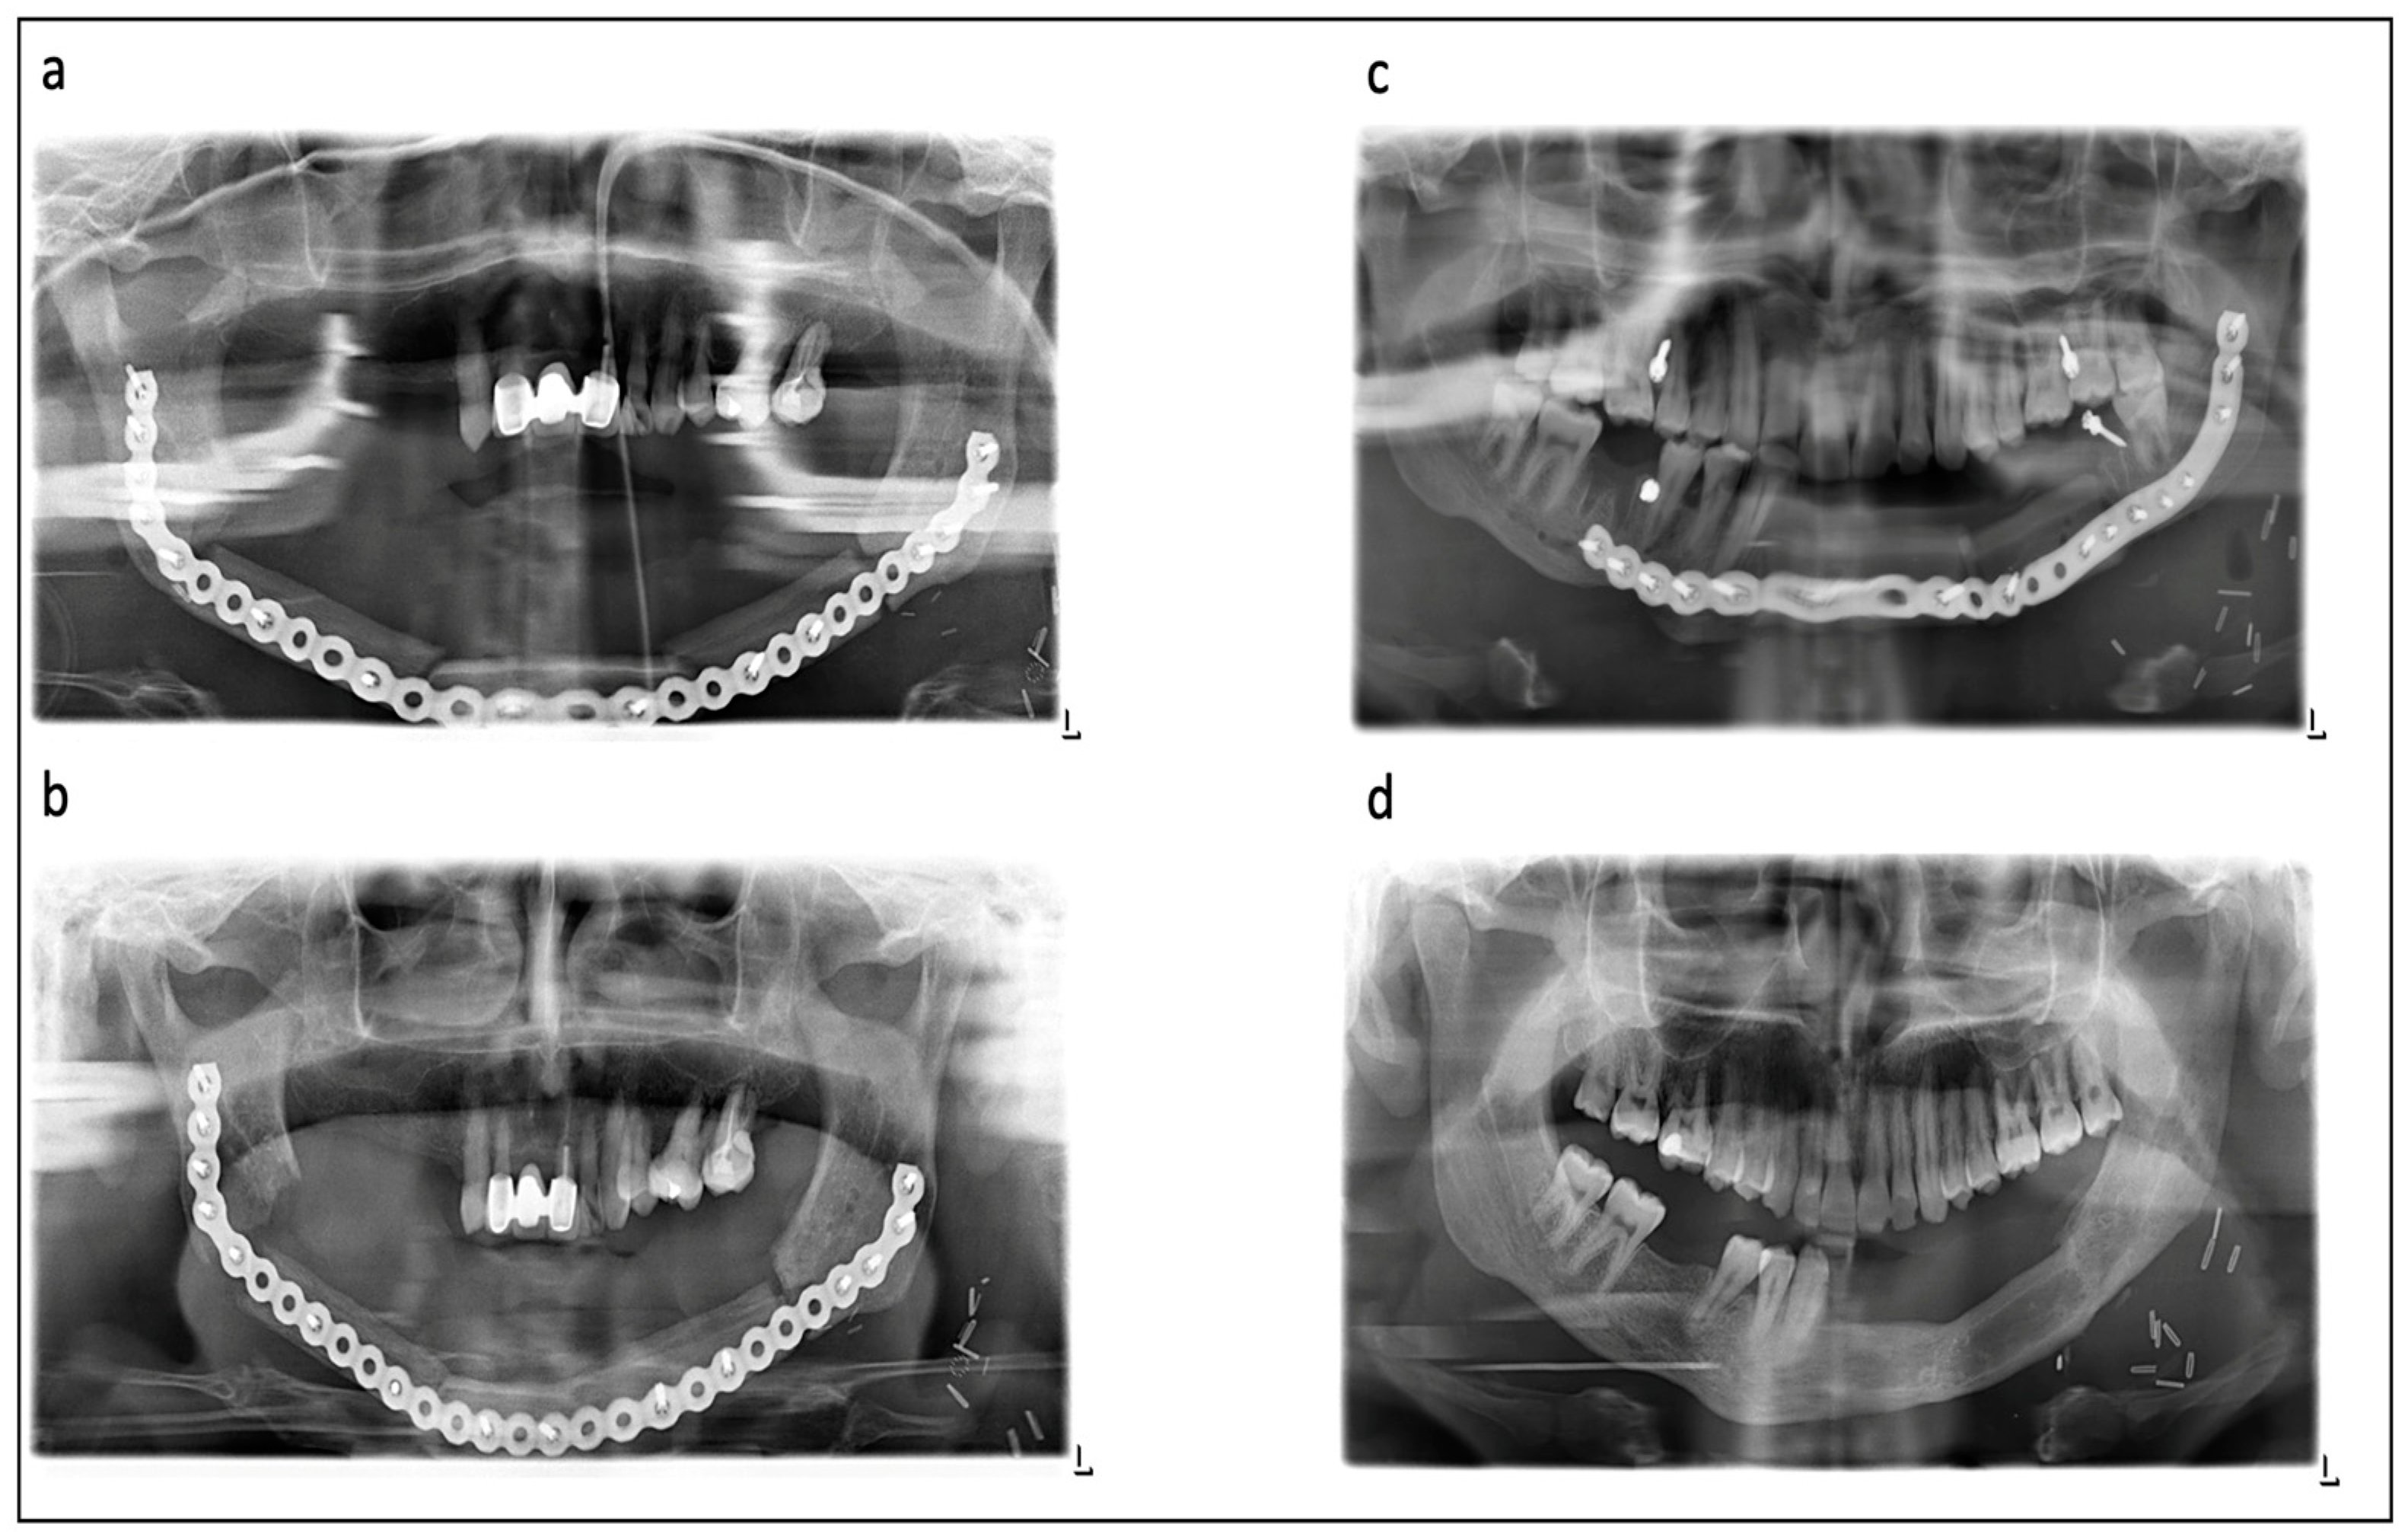

Figure 1.

Various examples for ossification in different radiographs: (a,b) show patient after preoperative radiotherapy, consecutive osteoradionecrosis of the mandible and reconstruction with a 3-segmented fibula. (a) Initial postsurgical radiograph with good contact between fibular segments in left canine area, moderate contact in right canine and right angle area and no contact in left angle area. (b) After 6 months, complete intersegmental ossification and nonossification between segments and original bone. (c,d) show young patient after gunshot wound and reconstruction with a two-segmental fibula. (c) Initial postsurgical radiograph with good contact between fibula segments and graft/native bone. (d) After 1 year, complete ossification of all contacts allowed for removal of the reconstruction plate.

Follow-up radiographs during healing were evaluated for quality of ossification as follows (Figure 1): no ossification (no sign of ossification vertically between the segments), partial ossification (less than 50% ossification between the segments) and complete ossification (more than 50% ossification between the segments). In the case of a diverse evaluation between the raters, a review was performed by two additional senior experts and a final statement was expressed.